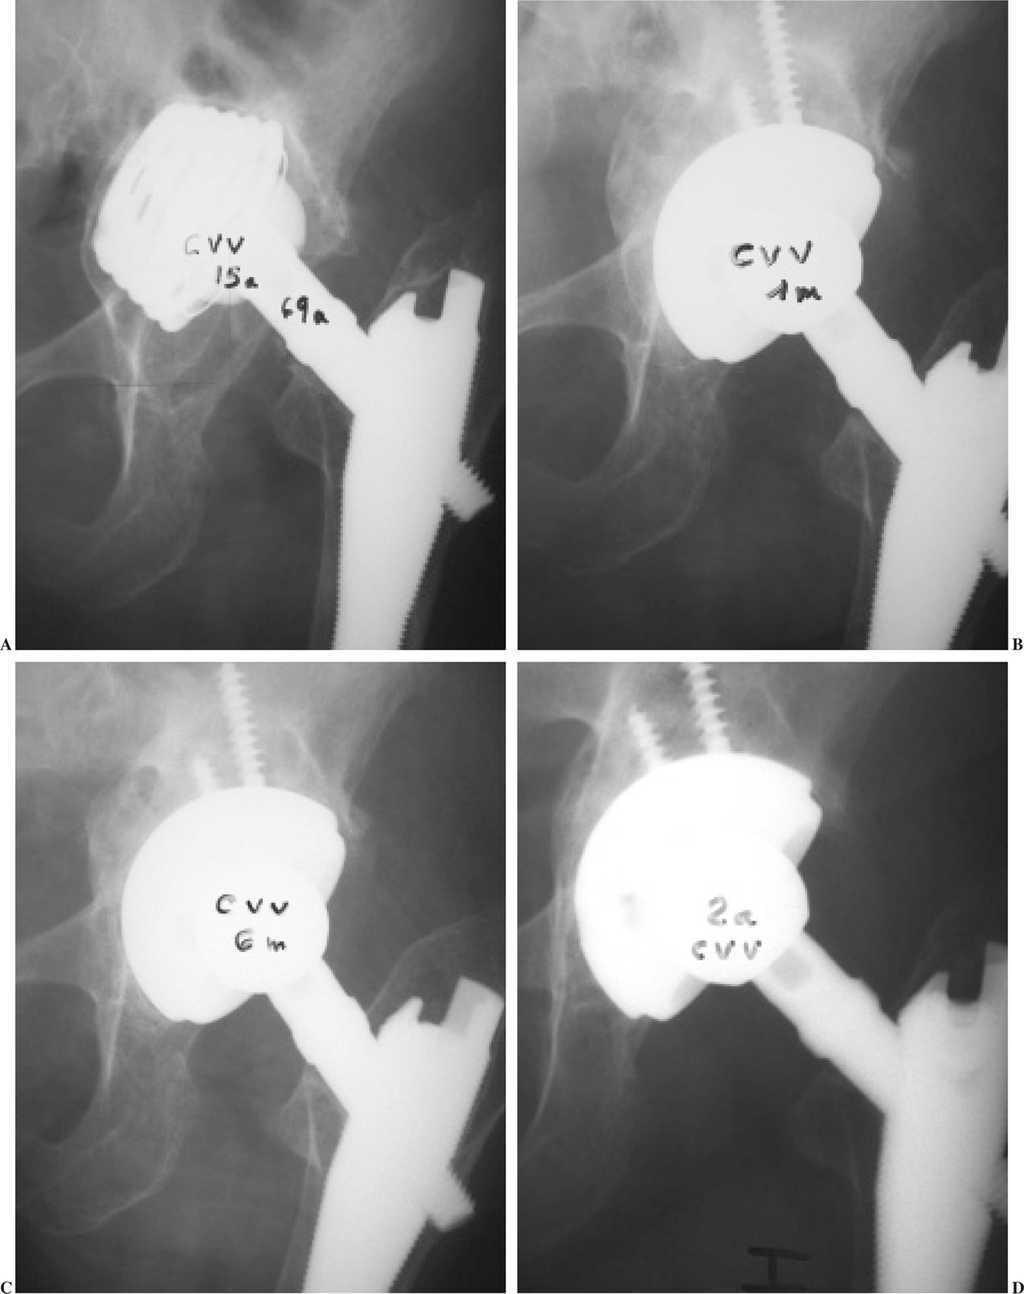

Figura 2.A) Paciente de 69 años con aflojamiento de cotilo de titanio roscado a los 15 años, con desgaste de polietileno, ascenso del implante superior a 3 cm, medialización con rotura de la línea de Köhler. B) Cotilo con recubrimiento de hidroxiapatita apoyado en su totalidad sobre injertos óseos de banco fragmentados impactados, al mes de la cirugía. C) y D) Remodelación progresiva de los injertos a 6 meses y 2 años, con formación de fondo y techo acetabular de aspecto normal.

Los injertos parecieron integrados con una buena remodelación ósea del techo y reconstrucción de la pared medial en 31 casos (73,8%) (figs. 1 y 2). Hubo reabsorción parcial del injerto en 4 casos (9,5%), con disminución del grosor inicial del injerto o reabsorciones mínimas lacunares. Fue difícil valorar en 7 casos (16,6%) por superposición del implante metálico y el injerto. Los casos de reabsorciones parciales o dificultad de interpretación radiológica no tuvieron traducción clínica.